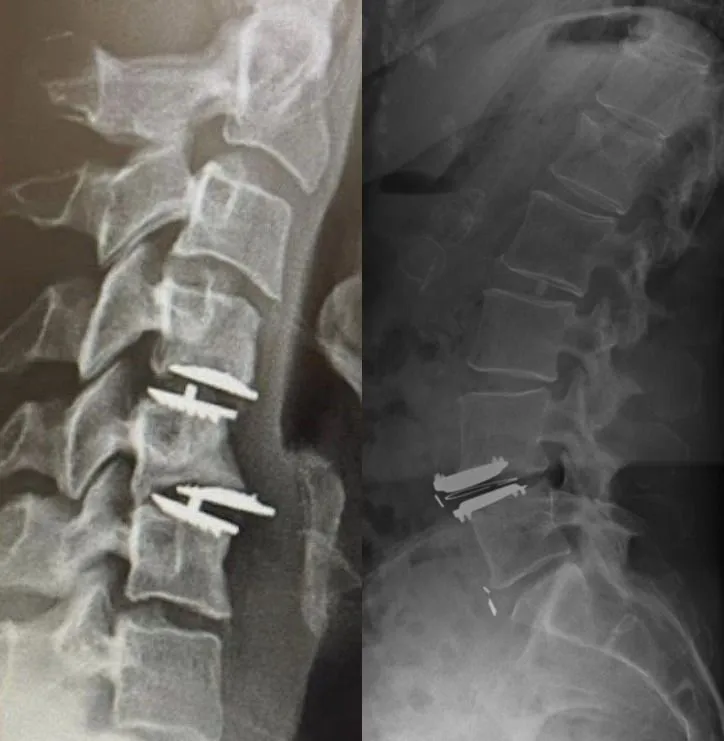

X-ray of a spine with metal screws and plates inserted.

Excessive Scar Tissue

X-ray of a neck showing metal screws and plates in the cervical spine.

Additional Surgery Likely

Side-by-side spinal X-rays showing vertebrae with surgical screws inserted.

Failed Back Surgery & Chronic Pain

Procedure fails to resolve pain, leading to failed back surgery syndrome and lifelong suffering.